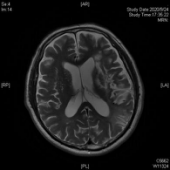

患者老李由于突发脑梗死,一觉醒来竟然听不懂别人的一句话,也说不出一个字,就连简单的“a”、“o”、“e”都说不出来。这对于作为教师的老李来说,无疑是晴天霹雳,当头一棒。经头颅核磁检查显示:老李的左侧大脑大面积脑梗死。老李是右利手,他的优势半球为大脑左半球,也就是支配我们语言的脑区。然而,不幸地是这个区域脑区几乎没有一丁点地儿在这场灾难中幸存,自发语极少,听觉理解、文字理解严重障碍,命名、复数、读词不能,听、说、读、写所有语言模式受到严重损害,诊断为完全性失语伴有言语失用。于是在他人的眼里,他似乎变得“又聋又哑”,既听不明白别人说什么也说不出来一句话,像是他的世界屏蔽了信号,接收不到任何语言的输入,也输出不了任何语言符号。这可急坏了老李的老伴,这以后可怎么办呀?